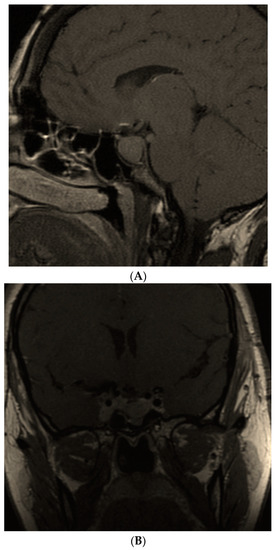

- Kasuki, L.; Neto, L.V.; Takiya, C.M.; Gadelha, M.R. Growth of an aggressive tumor during pregnancy in an acromegalic patient. Endocr. J. 2012, 59, 313–319. [Google Scholar] [CrossRef] [PubMed]

- Hannon, A.M.; Frizelle, I.; Kaar, G.; Hunter, S.J.; Sherlock, M.; Thompson, C.J.; O’Halloran, D.J.; Irish Pituitary Database Group. Octreotide use for rescue of vision in a pregnant patient with acromegaly. Endocrinol. Diabetes Metab. Case Rep. 2019, 2019, 19-0019. [Google Scholar] [CrossRef] [PubMed]

- Dicuonzo, F.; Purciariello, S.; De Marco, A.; Guastamacchia, E.; Triggiani, V. Inoperable Giant Growth Hormone-secreting Pituitary Adenoma: Radiological Aspects, Clinical Management and Pregnancy Outcome. Endocr. Metab. Immune Disord. Drug Targets 2019, 19, 214–220. [Google Scholar] [CrossRef]